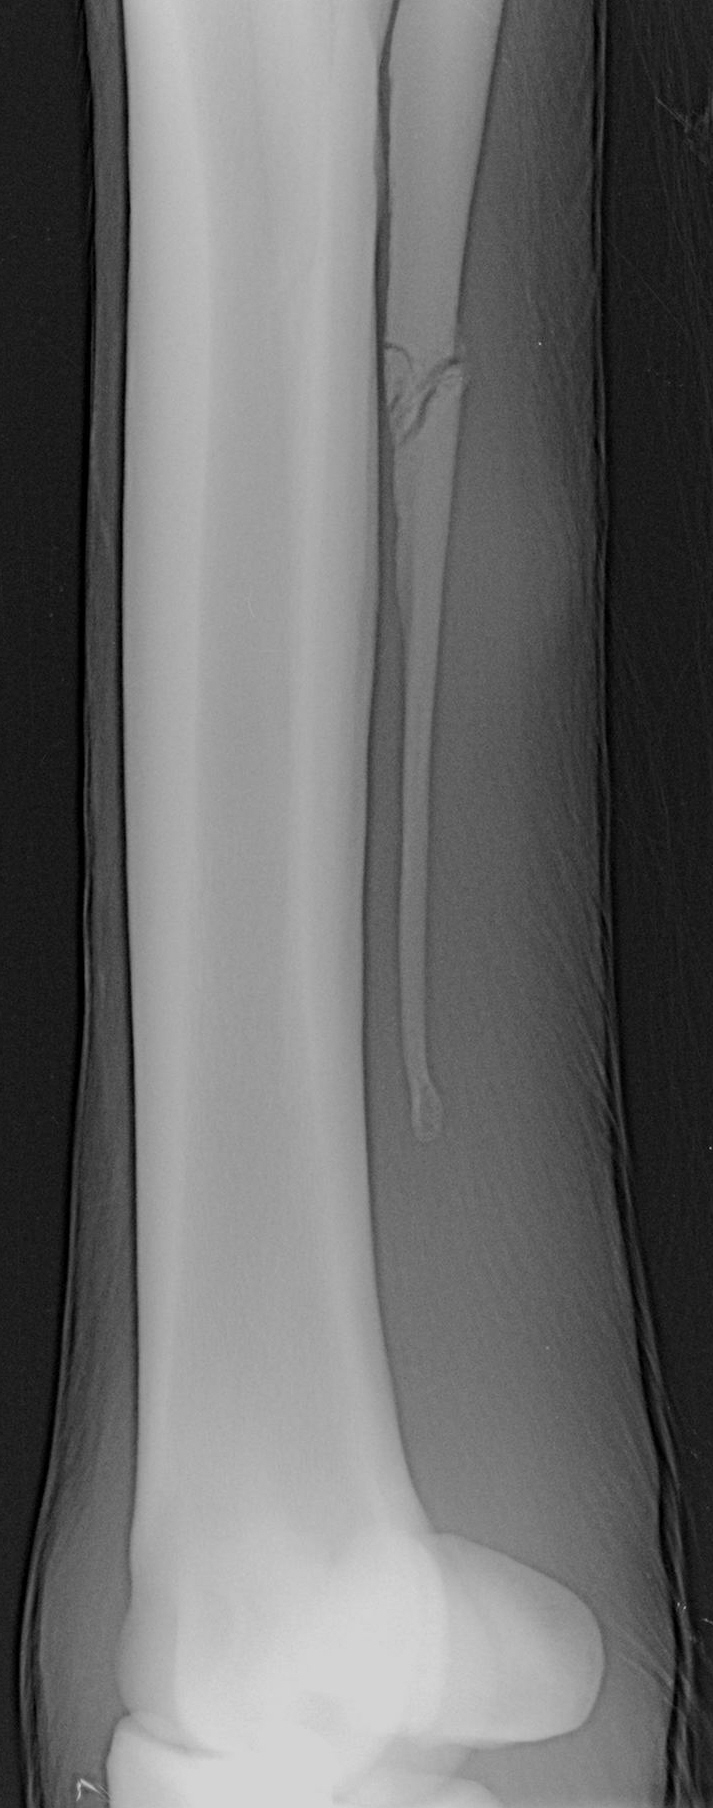

Gering- oder mittelgradige Lahmheiten sind in der Regel kein Notfall. Aber auch bei geringeren Lahmheiten sollte auf Selbstmedikation, abgesehen vom Rivanolverband bei kleinen Verletzungen, verzichtet werden. Nicht selten verbirgt sich hinter der geringen Lahmheit mit mehr oder weniger Schwellung eben doch mehr, wie das Bild mit dem Griffelbeinbruch zeigt.

Verletzungen im Röhrbeinbereich ziehen oft ein Griffelbein in Mitleidenschaft. Zum Ausschluss einer Fraktur des Griffelbeins sollte daher eine Röntgenaufnahme gemacht werden. Da die Griffelbeine kaum Last tragen, fehlt häufig der bei einer Fraktur erwartete Schmerz, weshalb die betroffenen Pferde oft nicht deutlich lahm sind.